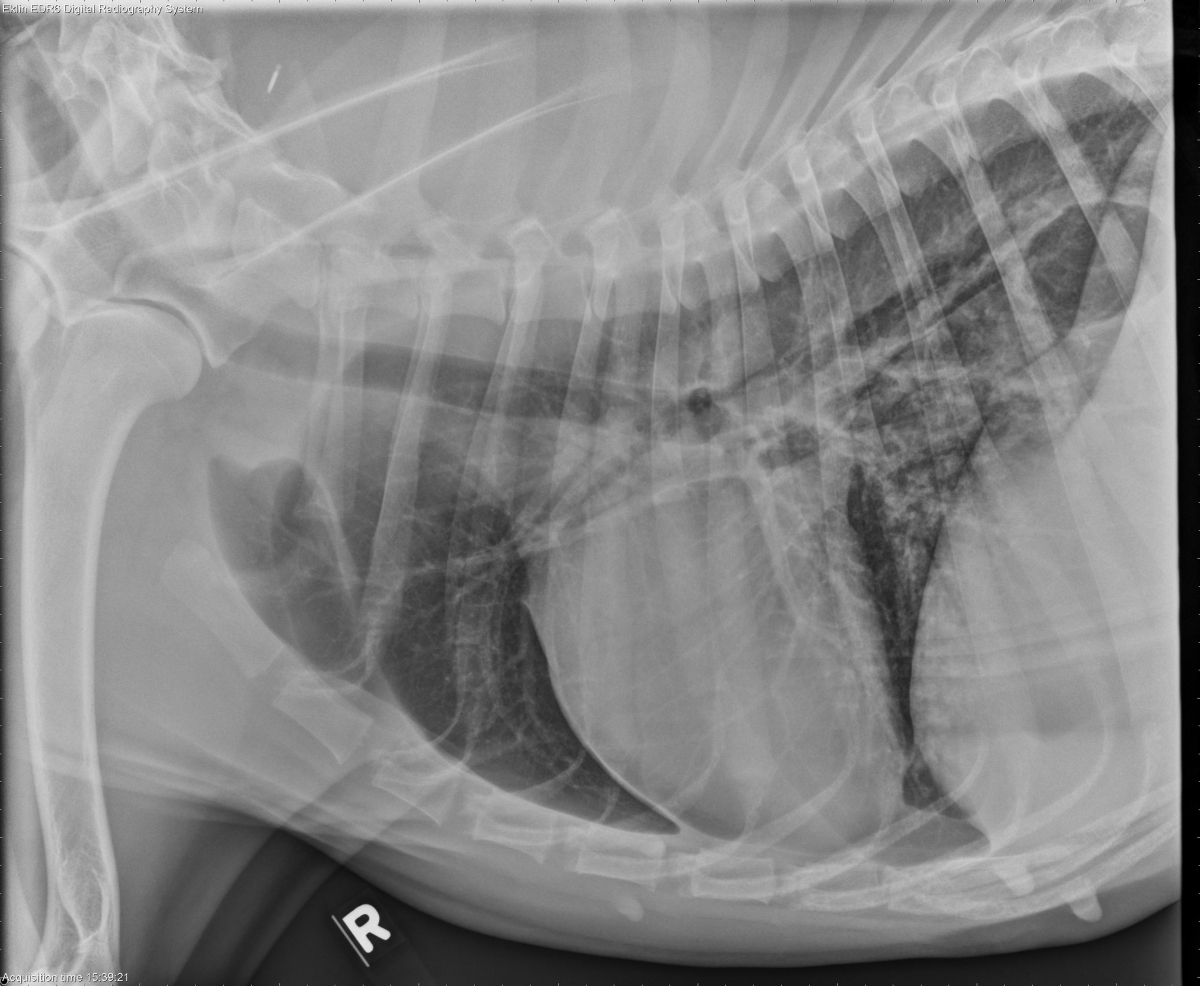

Today’s case is a 1.5-year-old female Great Dane with coughing and lethargy. What are your differential diagnoses?

R LAT Thorax

Findings

There is a cavitary lesion in the right caudal or accessory lung lobe visible on all projections. The wall of the pulmonary lesion is thickened and irregular. There is a bronchointerstitial pattern present in the accessory lung lobe. Small pleural fissure lines are present. There is no evidence of pneumothorax. The cardiovascular and musculoskeletal structures are normal.

Differential Diagnosis

Differential diagnoses for the cavitary pulmonary lesion include an abscess with associated pneumonia or a bulla with inflammation. The pleural fissure lines may indicate pleural thickening or a small pleural effusion.

Diagnosis

On CT images, the lesion was bridging the accessory and right caudal lung lobes. There was inflammatory change and pleural thickening surrounding the mass. The CT diagnosis was an abscess, likely secondary to a migrating foreign body.

Both the right caudal and accessory lung lobes were removed as there were extensive adhesions surrounding the lesion. An abscess was confirmed on histopathology. No plant material was found; however, there was a bone fragment within the abscess suggesting an inhaled etiology.